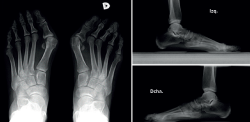

Para realizar una correcta evaluación radiológica se deben realizar al menos 2 proyecciones en carga, una proyección dorsoplantar y una lateral del pie (Figura 2).